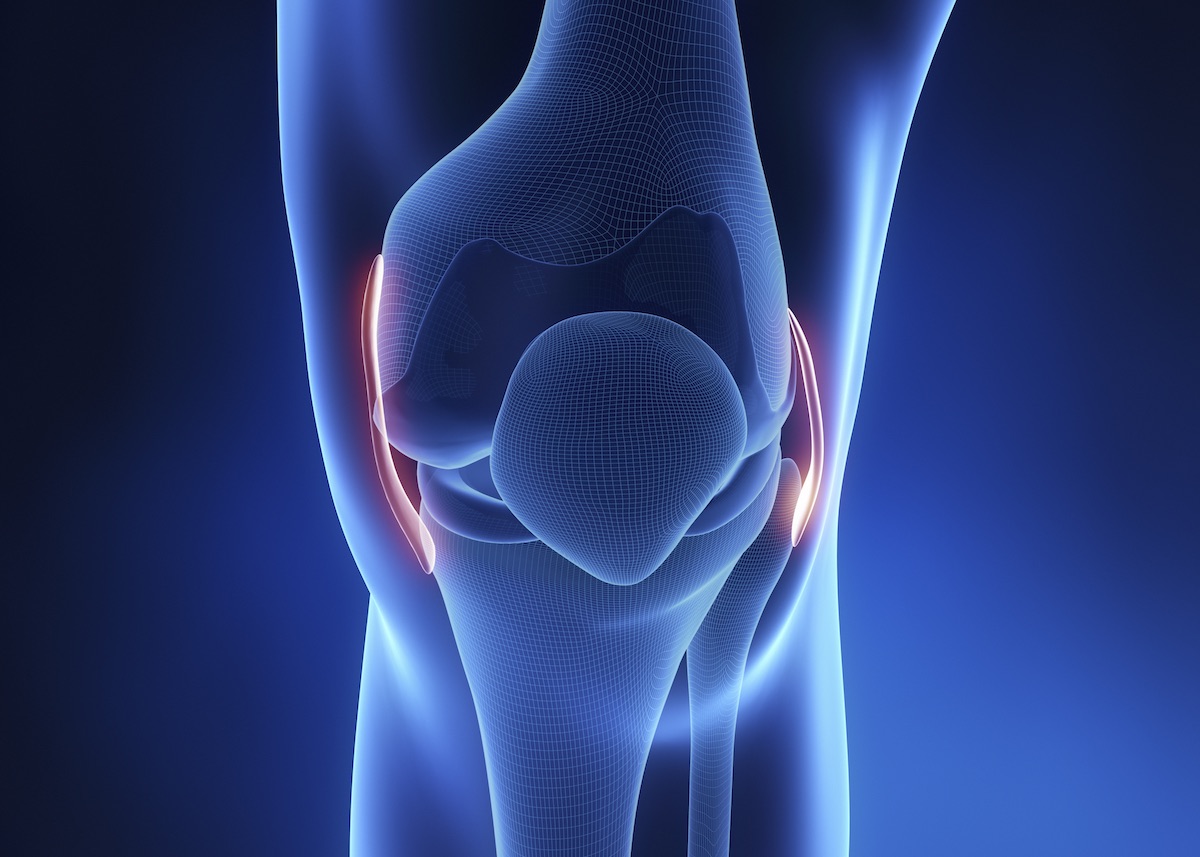

Причины и лечение травм коленного сустава